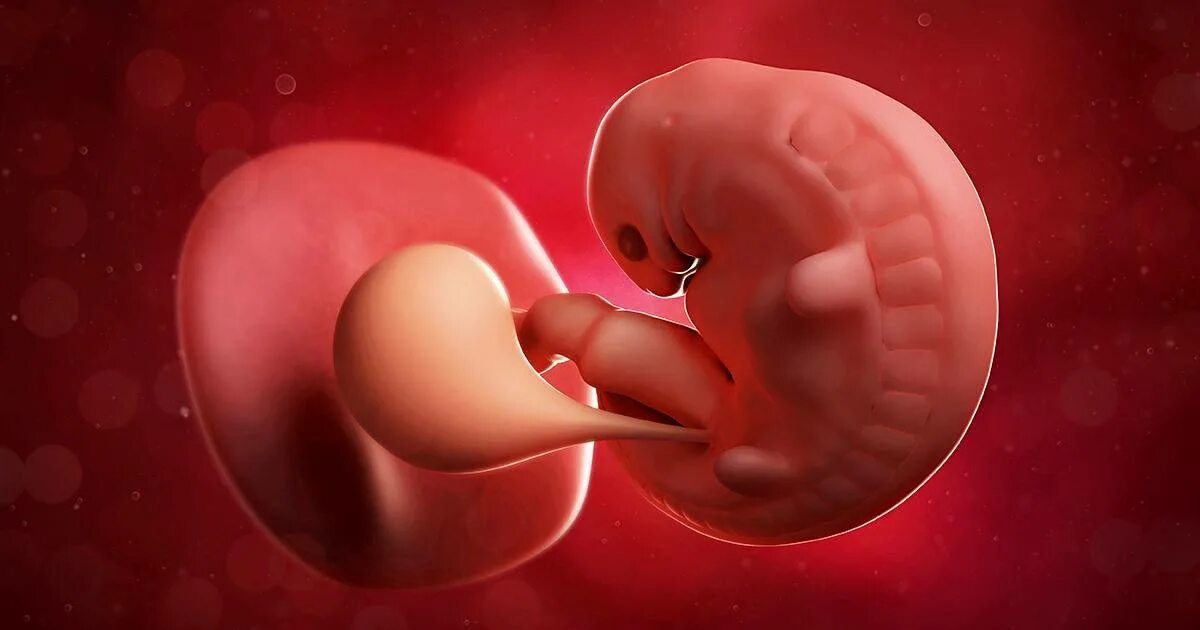

6 недель беременности как выглядит эмбрион